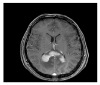

Primary Central Nervous System Lymphoma (PCNSL) is a rare neoplasm that can involve brain, eye, leptomeninges, and rarely spinal cord. PCNSL lesions most typically enhance homogeneously on T1-weighted magnetic resonance imaging (MRI) and appear T2-hypointense, but high variability in MRI features is commonly encountered. Neurological symptoms and MRI findings may mimic high grade gliomas (HGGs), tumefactive demyelinating lesions (TDLs), or infectious and granulomatous diseases. Advanced MRI techniques (MR diffusion, spectroscopy, and perfusion) and metabolic imaging, such as Fluorodeoxyglucose Positron Emission Tomography (FDG-PET) or amino acid PET (usually employing methionine), may be useful in distinguishing these different entities and monitoring the disease course. Moreover, emerging data suggest a role for cerebrospinal fluid (CSF) markers in predicting prognosis and response to treatments. In this review, we will address the challenges in PCNSL diagnosis, assessment of response to treatments, and evaluation of potential neurotoxicity related to chemotherapy and radiotherapy.